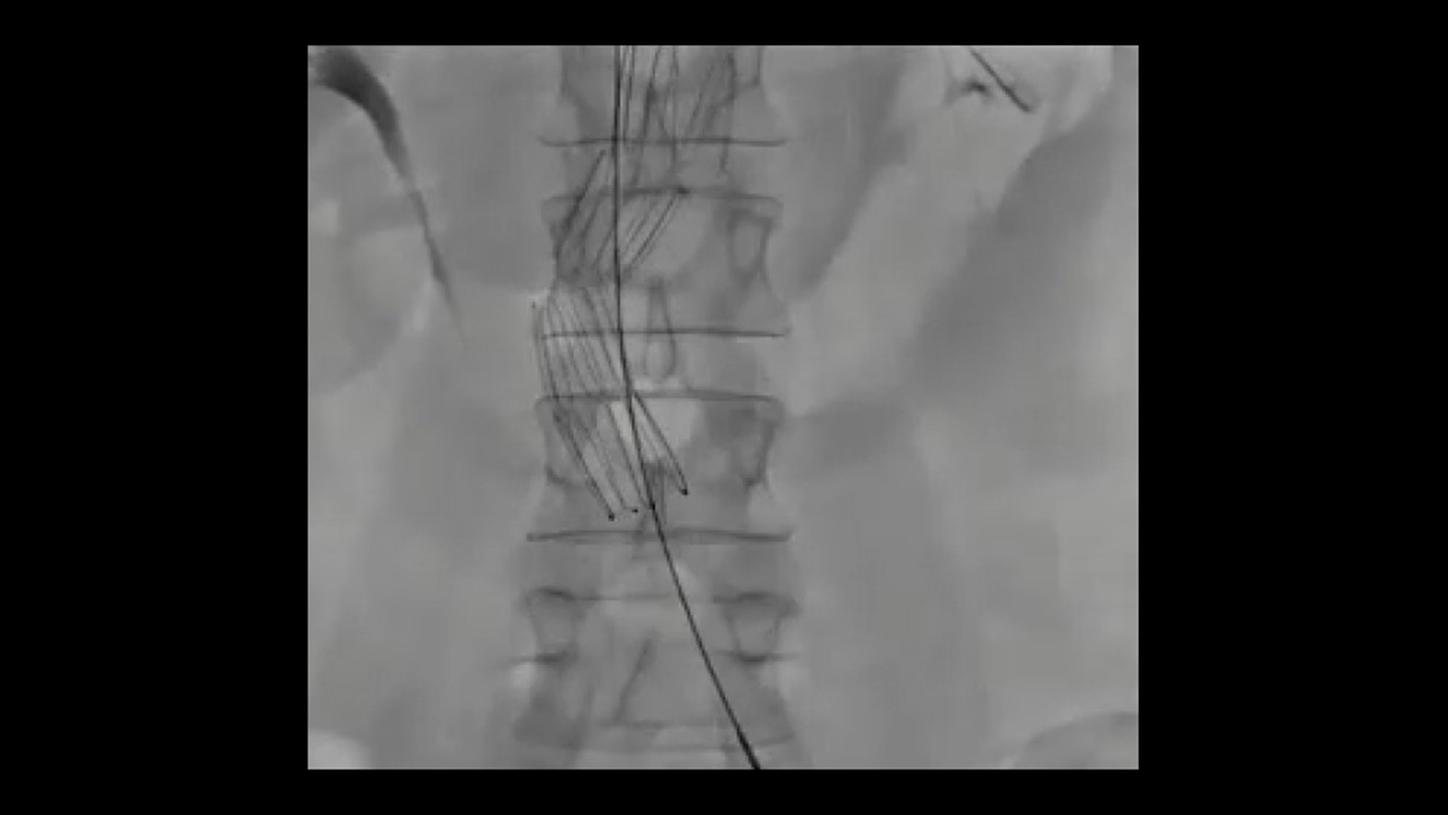

During minimally invasive procedures, it is critical to have a clear view of anatomies and devices. Yet complex imaging tasks or challenging patient conditions often impact image quality. OPTIQ AI delivers constant image quality1 defined by CNR in support of the ALARA principle, independent of patient or C-arm angulation. On top, an AI-powered algorithm reduces image noise in real time across different 2D imaging modes.

Make AI-powered imaging and clear insights your standard during interventions – with OPTIQ AI.

Future-focused IR imaging for a broad procedure mix

Discover how leading clinicians are transforming interventional radiology with Siemens Healthineers technologies. From ultra-fast 3D imaging to laser-guided needle procedures, the ARTIS icono ceiling powered by OPTIQ and syngo DynaCT are redefining what’s possible in IR. Explore real-world cases, expert insights, and the future of image-guided therapy.